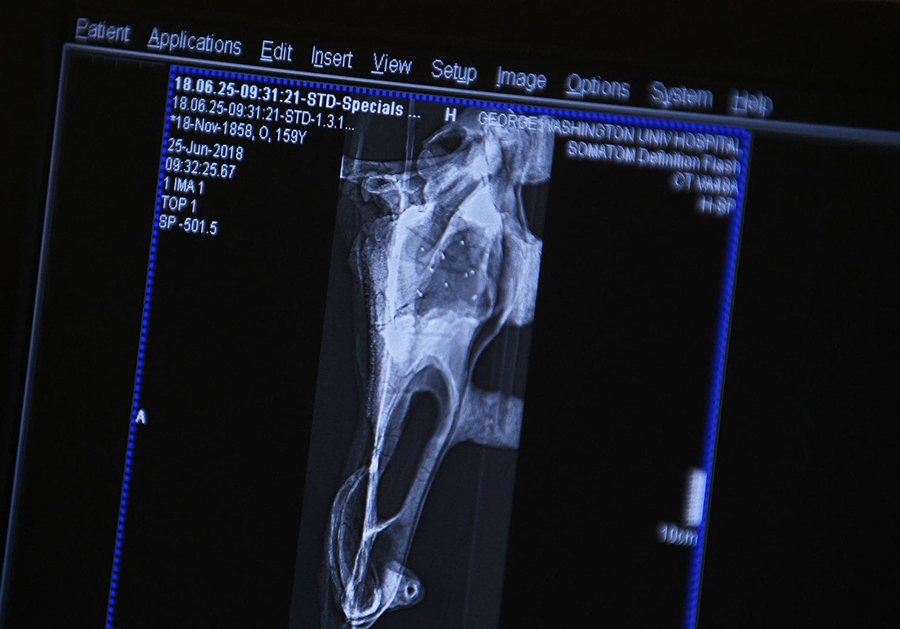

The “patient” was a 68-million-year-old skull of an edmontosaurus — one type of a duck-billed dinosaur — that belongs to the Smithsonian National Museum of Natural History. The 150-pound skull and jaw were getting a CT scan for an upcoming museum exhibition.

The fossil was transported in two parts, the tall and sloping skull in one specially crafted protective case and its lower jaw in another. The first and largest piece presented the biggest challenge for CT supervisor Bruce Payne and radiologist James Earls. They scanned the skull upright first but couldn’t get the top edge in the frame because it was nestled in its protective case. The medical team wanted to take it out of the case — something Steve Jabo, the museum’s fossil preparator, wanted to avoid — so they decided to send it through the machine upside down, resting in the case’s top.

What and how these giant creatures ate is the subject of an interactive digital display that will be part of the museum’s reimagined Fossil Hall. The digital images collected on Monday create the foundation for this display.

The scanned skull will be featured in the digital display intended to explain how the dinosaur ate. The hospital delivered the standard medical imaging files to the museum, which will use them to create a 3-D version. The digital exhibit will showcase three dinosaur skulls and show how their bones, muscles, ligaments and tendons worked together. The display will allow the upper and lower jaws to separate to give visitors views inside the mouth. In addition to exploring the skulls, the interactive exhibit will allow visitors to try to “feed” each dinosaur.

“We can see the internal structure, all of the nasal openings, the vein density, how everything is formed in there,” Jabo explained.